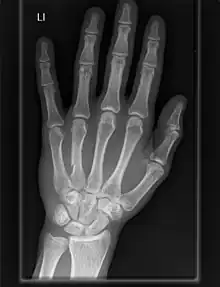

The carpometacarpal (CMC) joints are five joints in the wrist that articulate the distal row of carpal bones and the proximal bases of the five metacarpal bones.

Fingers

- The second metacarpal articulates primarily with the trapezoid and secondarily with the trapezium and capitate.

- The third metacarpal articulates primarily with the capitate,

- The fourth metacarpal articulates with the capitate and hamate.

- The fifth metacarpal articulates with the hamate.

Among themselves, the four ulnar metacarpals also articulates with their neighbours at the intermetacarpal articulations.[7]